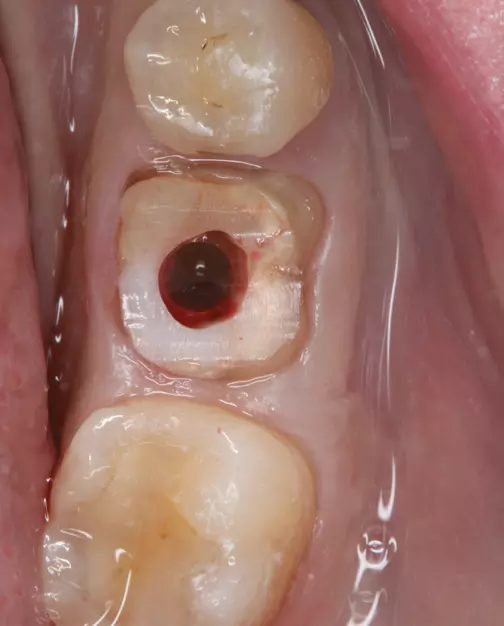

Der in Abbildung 4 gezeigte Emergenzwinkel und Emergenzprofil ist zum einen der Weichgewebshöhe als auch der Implantatposition geschuldet. Bei solchen Situationen, die häufig im Unterkierferseitenzahnbereich auftreten, muss sich der Chirurg vor der Implantation folgende Gedanken machen:

30° erstellt werden.“ class=“wp-image-26384″/>

- Wie hoch müsste das Weichgewebe in dieser Region sein, um ein Abutment mit einem Emergenzwinkel von <30° und einem konkaven Emergenzwinkel zu gestalten?

- Ist die weichgewebige Augmentation bis zu der erforderlichen Höhe chirurgisch zu realisieren?

Ist die vorhandene Weichgewebshöhe nicht hoch genug um einen Emergenzwinkel von <30° und ein konkaves Emergenzprofil zu gewährleisten, muss die Frage nach der weichgewebigen Augmentierbarkeit gestellt werden.